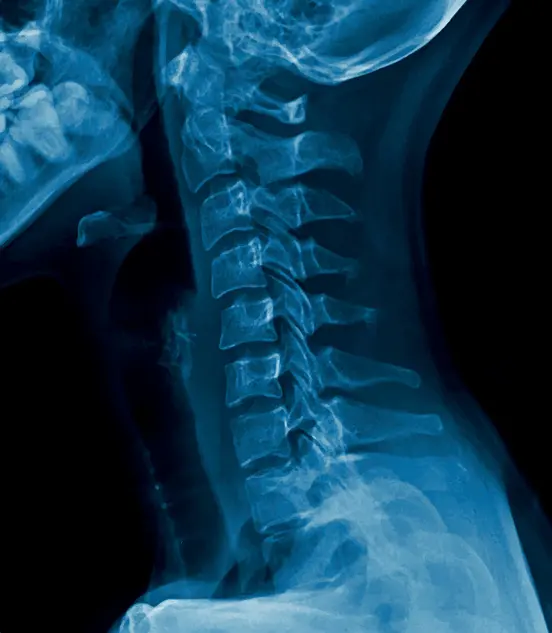

Teleradiology reporting is the process of interpreting and reporting medical images remotely. This technology allows healthcare facilities to provide around-the-clock radiology reporting services, ensuring quick and accurate diagnosis and treatment for patients.